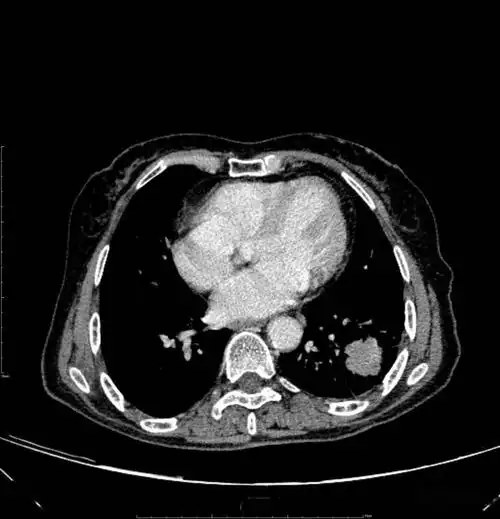

图片是患者ct平扫和多期增强扫描(动脉期,静脉期,平衡期或延迟期)的

胸部ct平扫